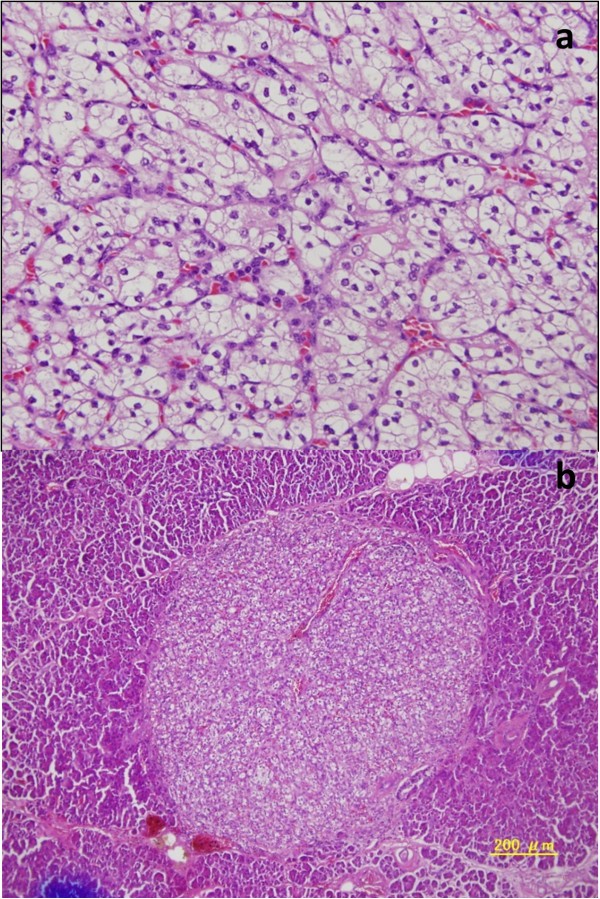

A 63-year-old woman had undergone left nephrectomy for RCC at our hospital 13 years previously. After 5 consecutive years of follow-up, she underwent an annual medical examination. Abdominal ultrasonography (US) revealed an abnormal mass in the body of the pancreas. CT revealed two lesions: a low-density mass (15 mm in diameter) in the pancreatic body that displayed rim enhancement and a homogeneously enhanced mass (8 mm in diameter) in the head (Figure 1). Magnetic resonance imaging (MRI) did not show enhancement in either lesion. FDG-PET did not show any abnormal metabolic activity in the pancreas. To allow a pathological diagnosis, endoscopic ultrasonography (EUS)-guided fine-needle aspiration biopsy was performed, but only necrotic tissue was obtained from the specimen. Although the radiographic features of the lesions were different, pancreatic metastases from RCC were strongly suspected because of the patient’s history of RCC. We noted the following from the laboratory findings: DUPAN-2, <25 U/ml (normal, <25 U/ml); Span-1, 2.3 U/ml (normal, <30 U/ml); carcinoembryonic antigen, 1.7 ng/ml (normal, <5.0 ng/ml); carbohydrate antigen 19-9, 2.6 U/ml (normal, <37 U/ml) and gastrin, 480 pg/ml (normal, <200 pg/ml). The patient underwent pylorus-preserving pancreaticoduodenectomy using the Imanaga method [18]. For the R0 resection, an extended pancreaticoduodenectomy was required rather than a classical resection. Intraoperative US revealed a low echoic mass with a bright halo and peripherally enriched blood flow in the body and a low echoic mass with homogeneously enriched blood flow in the head. Gross pathological examination revealed a 15 mm × 13 mm tumor occupying the body of the pancreas and another 8-mm tumor in the uncinate process of the pancreas. The head lesion was soft, whereas the body lesion was firm in consistency. The cut surface of the head lesion was yellow, whereas that of the lesion in the pancreatic body was grayish-white. Metastatic tumor cells homogeneously occupied the tumor in the head of the pancreas, and the firm lesion in the body of the pancreas showed a necrotic change in the center, which was surrounded by viable tumor cells and a fibrous capsule, identified as a low-density area on a CT scan (Figure 2). Immunohistochemically, the tumors were positive for CD10 and negative for chromogranin A and synaptophysin (Figure 2). Microscopic examination revealed large epithelial cells with clear cytoplasm and eosinophilic nuclei arranged in alveolar structures with abundant vascularity (Figure 3a). In addition, histological examination revealed another 1-mm occult micrometastatic lesion in the head of the pancreas (Figure 3b). The harvested lymph nodes and surgical margins were free of malignancy. Taken together, the pathological findings indicated that the lesions were metastases from RCC, and the thick enhanced rim of the body lesion was believed to be composed of viable RCC cells with high vascularity. The postoperative course was uneventful, and to date the patient has survived for 6 months without any evidence of recurrence or metastasis.